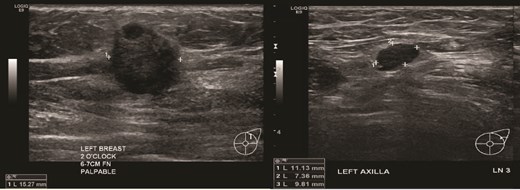

Patient C, aged 70, had no significant past medical history and initially presented to Otolaryngology with right-sided cervical lymphadenopathy. Excision biopsy confirmed a diagnosis of diffuse large B cell lymphoma (DLBCL). She then reported a 3-month history of a left breast lump. Clinical examination and imaging revealed a 20 mm lesion associated with ipsilateral axillary lymphadenopathy (Figs 7 and 8). Triple assessment confirmed triple negative invasive ductal carcinoma in the breast, whilst there were follicular cells in the nodes (Fig. 9). She underwent systemic chemotherapy for stage III diffuse large B-cell lymphoma using Rituximab, cyclophosphamide, doxorubicin, vincristine, and prednisolone (R-CHOP) protocol followed by weekly Paclitaxel for the concurrent breast cancer. She achieved clinical remission for lymphoma. Subsequently she underwent breast conserving surgery with sentinel node biopsy, and adjuvant chest radiotherapy.

(Left) Ultrasound image of the left breast hypoechoic lesion; (Right) Ultrasound image of one of several enlarged lymph nodes with effacement of fatty hilum.

(Left) Mammography cranial-caudal view of left breast; (Right) Mammography mediolateral oblique view of the left breast: Left upper outer breast spiculated mass with minimal architectural distortion.